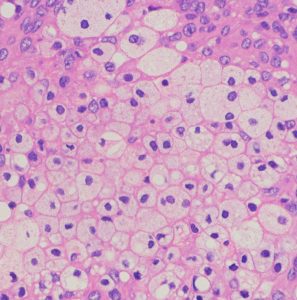

xanthomatous change 黄色腫様の髄膜腫

小脳橋角部に発生した髄膜腫ですが,手術中に見た目に真っ黄色で柔らかく,繊維成分のない壊れやすい脂肪組織を摘出しているようでした。

xanthomaとも表現できるほどfoamy macrophagesの浸潤の目立つ組織です。

MIB-1染色率は8-10%と高く,臨床的にはグレード2に近い性格を示すものです。